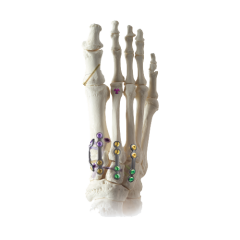

Explore our broad range ofOrthopedic Products

We are dedicated to improving the quality of life of patients suffering with bone and joint problems by delivering the latest medical devices that are proven to be effective and backed by scientific studies and research

• Surgical Devices